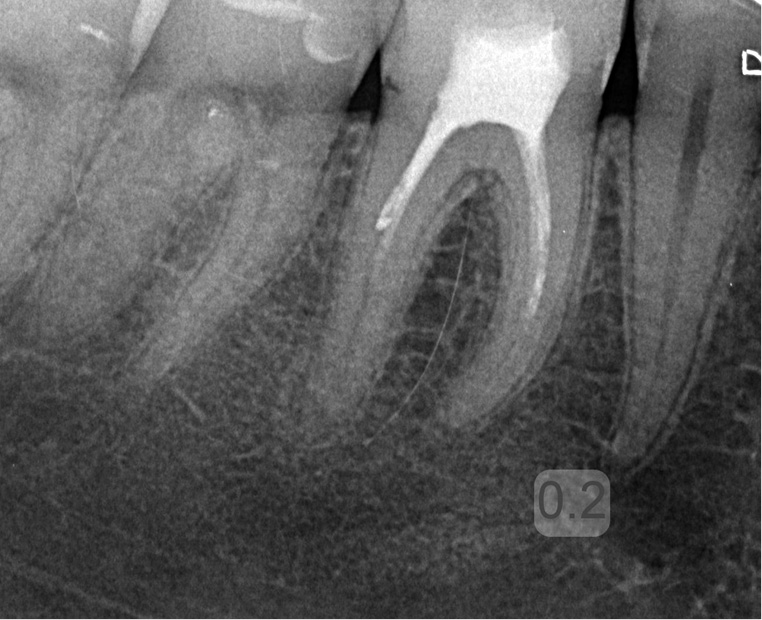

Powtórne leczenie endodontyczne zęba 46 – przypadek kliniczny

TITLE: Root canal retreatment of tooth 46 – a clinical case

STRESZCZENIE: W artykule omówiono wskazania i przeciwwskazania do powtórnego leczenia kanałowego. Przedstawiono przypadek kliniczny powtórnego leczenia endodontycznego.

SUMMARY: The article discusses indications and contraindications for root canal retreatment. A clinical case of endodontic retreatment is presented.

Dzięki ciągłemu rozwojowi endodoncji istnieje możliwość powtórnego leczenia endodontycznego zębów (ang. retreatment). Często pozwala to na zachowanie zęba, który pierwotnie skazany byłby na ekstrakcję. Z różnych przyczyn zdarza się, że leczenie endodontyczne nie zakończyło się sukcesem.